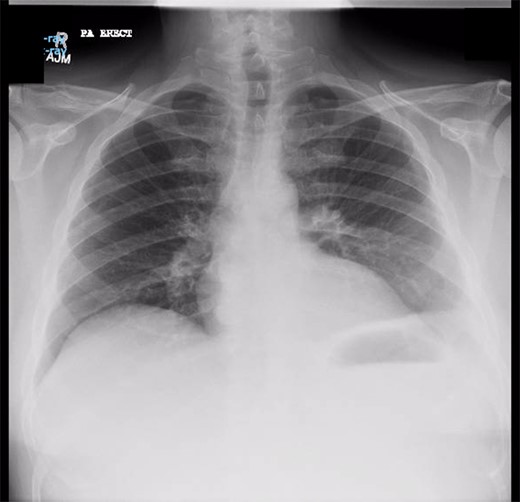

Chest X-ray in ICU following drainage showed what was thought to be Pneumomediastinum (Figs 1 and 2), and given this concern he was referred to the Cardiothoracic service. Subsequent CT suggested a large loculated hydro-pneumothorax, which in retrospect represented the drained Pseudocyst communicating through the diaphragm (Figs 3 and 4).

Sagittal view CT Chest revealing large residual space with loss of left lung volume due to the pseudocyst. Image post-transgastric drainage.